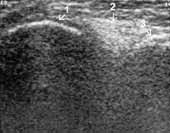

поражении (при ревматоидном артрите) также отмечается увеличение сумки с наличием

избытка жидкости, но количество жидкости обычно больше, чем при остеоартрозе,

она чаще неоднородная, обычно более «гиперэхогенная», синовиальная оболочка

утолщена до 1–3 мм и более (Рис. 3).

Рис. 3. Ревматоидный артрит, III стадия. Выраженное увеличение

b. suprapatellaris с наличием неоднородной жидкости и пролиферацией

синовиальной оболочки (+).